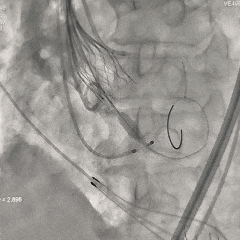

脱钩后造影

无窦侧深度约瓣上2mm,小弯侧深度基本零位,瓣膜植入位置尚可,瓣架形态呈现微倒梯形,可见少量瓣周漏,右冠显影正常

左冠切线位评估

左冠导管造影,可见左冠显影可,考虑导管挤压瓣叶可能,决定将导管拉出冠脉口再次造影评估

左冠再次造影评估

导管拉出左冠口后造影,可见冠脉灌注正常,瓣叶未超过冠脉开口

最终评估

超声测量AVmax=2.1m/s,PGmax=17mmHg,提示少量瓣周漏,间隔侧瓣架深度为真实瓣环零位

考虑球囊后扩的操作会进一步增加冠脉阻挡风险,并存在较高瓣膜上跳风险,综合患者情况可,决定不再进行球囊后扩。